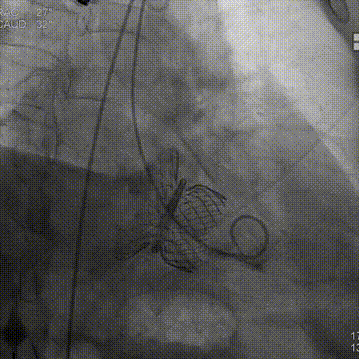

随后在超声引导下进行房间隔穿刺,最终穿刺高度约3.4cm,顺利建立经房间隔入路。而后沿成环导丝于二尖瓣环下植入固定环,通过DSA及3D超声确认固定环完全关闭且位置合适。沿股静脉送入HighLife TSMVR瓣膜,首先释放瓣膜心室端,随后牵拉输送器,超声下观察,使瓣膜心室端与固定环充分贴合,旋即保持拉力并释放瓣膜心房端,人工瓣膜脱钩,在固定环的辅助下,于二尖瓣瓣环平面完成自同轴,最后逐步撤出人工瓣膜输送系统和固定环输送系统。即刻超声评估提示二尖瓣返流完全消失,无瓣周漏,人工瓣膜植入位置理想,形态良好,跨瓣压差1mmHg;LVOT压差6mmHg,无左室流出道梗阻风险;房间隔4mm左向右分流,无即刻封堵指征。手术成功完成!

即刻左室造影

术后即刻超声评估